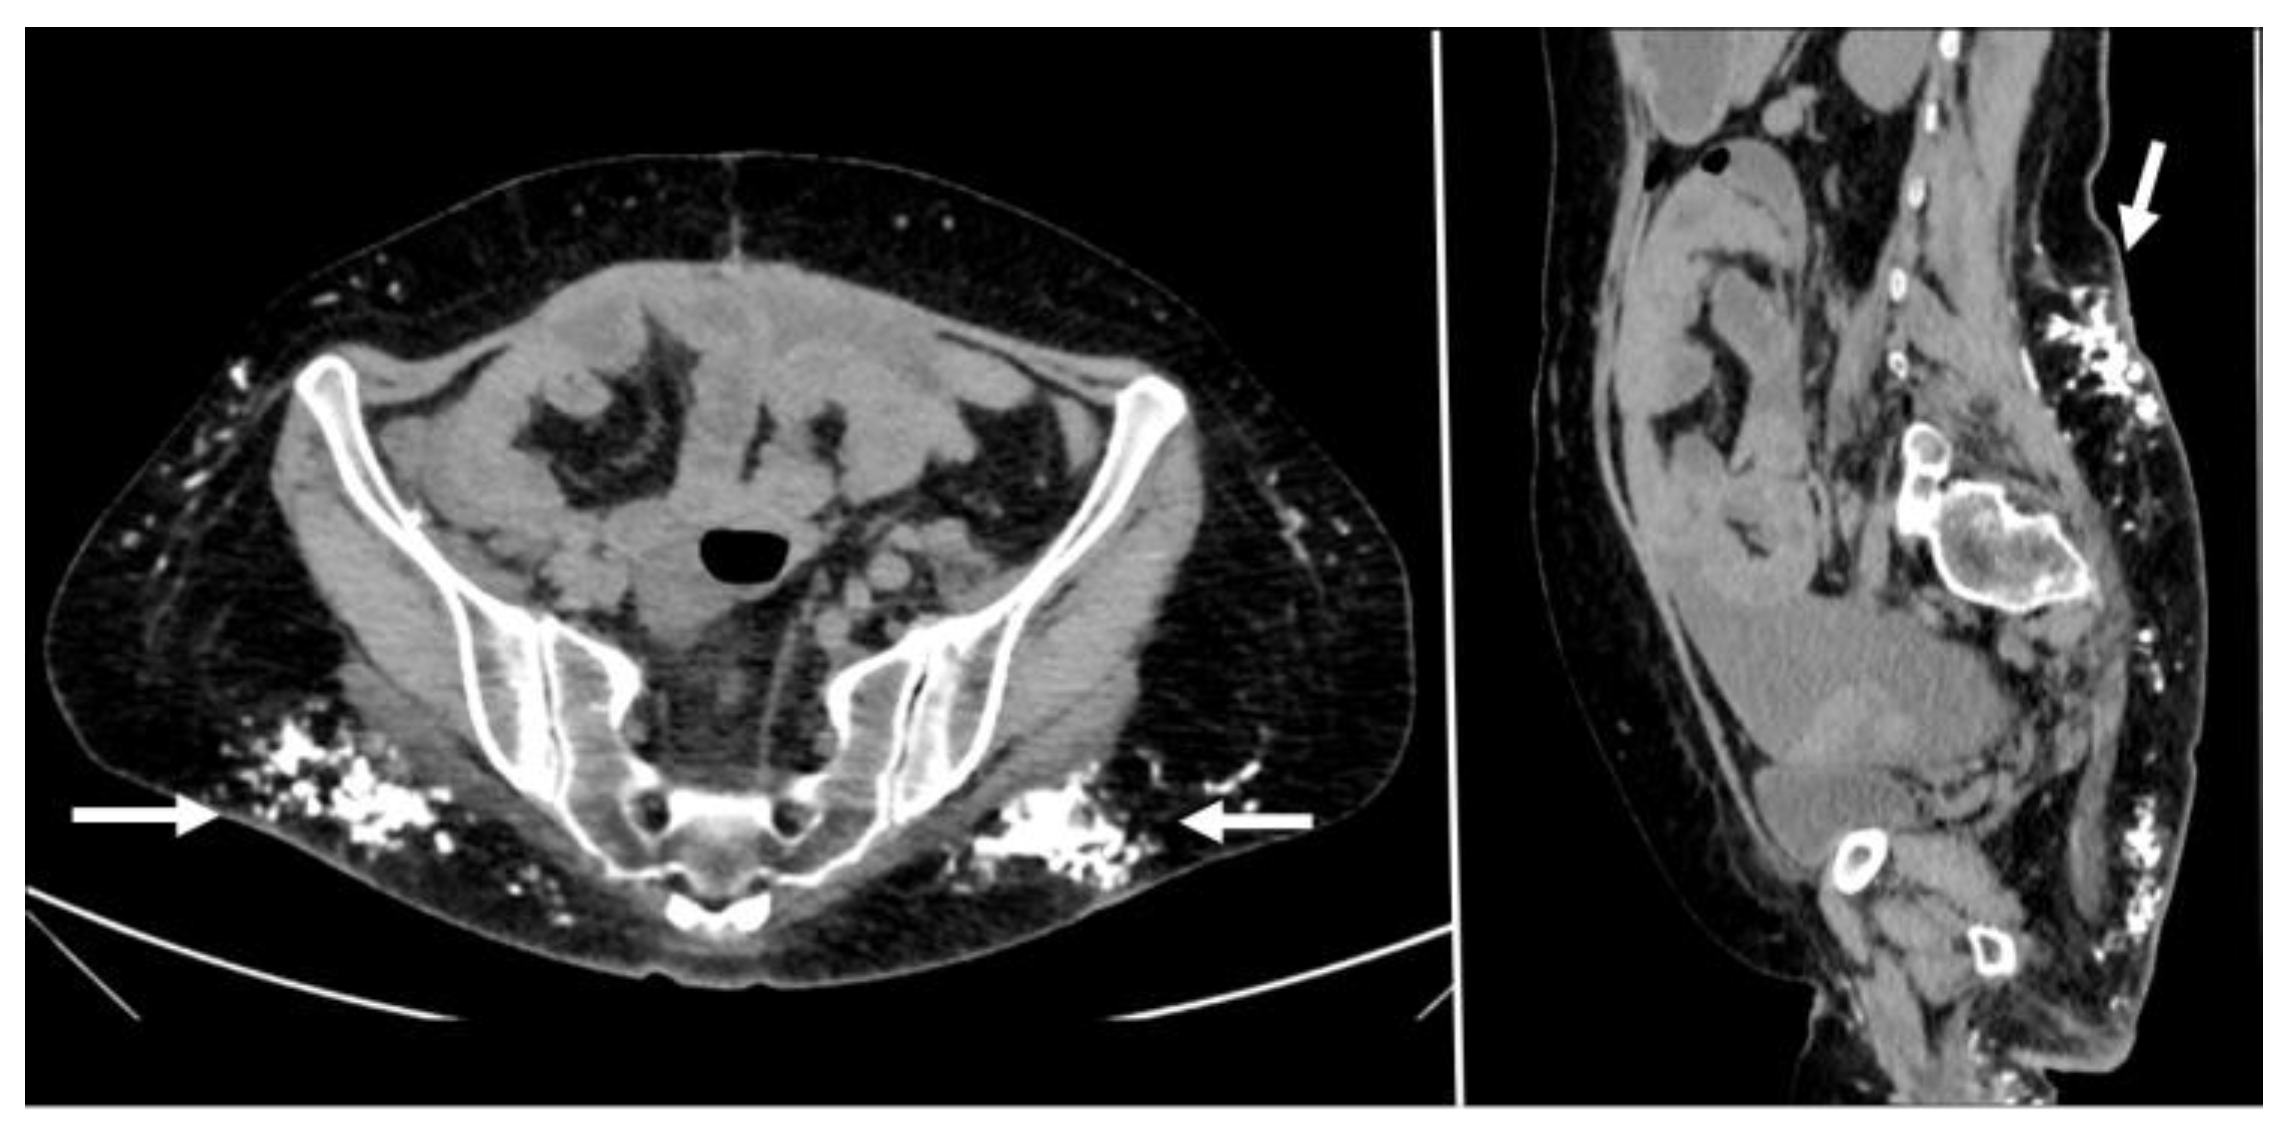

5.3. Subcutaneous Drugs